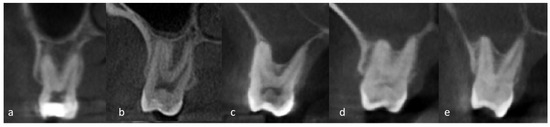

| Teeth condition | Vital | 717 | 56.5 |

| Restoration | 317 | 25.0 | |

| Failed RCT | 156 | 12.3 | |

| RCT | 51 | 4.0 | |

| Remaining root | 15 | 1.2 | |

| Implant | 13 | 1.0 | |

| Tooth condition | RCT | 1.43 | 0.68, 2.98 | 0.34 |

| Failed RCT | 2.87 | 1.65, 4.42 | <0.001 * | |

| Restoration | 1.64 | 1.14, 2.36 | 0.008 * | |

| Implant | 0.25 | 0.05, 1.35 | 1.12 | |

| Remaining root | 1.78 | 0.44, 7.01 | 0.42 | |

| Vital | Reference | |||